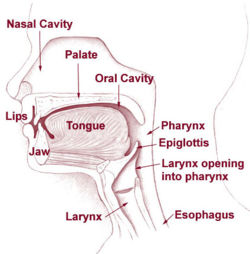

جوف الأنف أو الحفرة الأنفية إنگليزية: Nasal Cavity هو الجزء العميق من الأنف والممتد من المنخرين في الأمام وحتى المنعرين في الخلف[1][2]، أي حتى البلعوم في الخلف.[3] يقسم جوف الأنف إلى قسمين أيمن وأيسر بواسطة بنية عظمية غضروفية تدعى حاجز الأنف أو الوتيرة.[1]

الجدار السفلي

يسمى أرضية الأنف أو قاع الأنف ويتمثل بالحنك الصلب. يفصل الحنك الصلب جوف الأنف عن جوف الفم[1][2] وتتشكل ثلاثة أرباعه الأمامية من الناتئين الحنكيين للفكين العلويين في حين يتشكل ربعه الخلفي من الصفيحتين الأفقيتين للعظمين الحنكيين. أرضية الأنف مقعرة قليلاً بالعرض وأفقية تقريباً بالمستوى الأمامي الخلفي. يرى أحيانا في الجزء الأمامي الأنسي من الأرضية انخفاض صغير يدعى الردب الأنفي الحنكي.[6]

الاتصالات